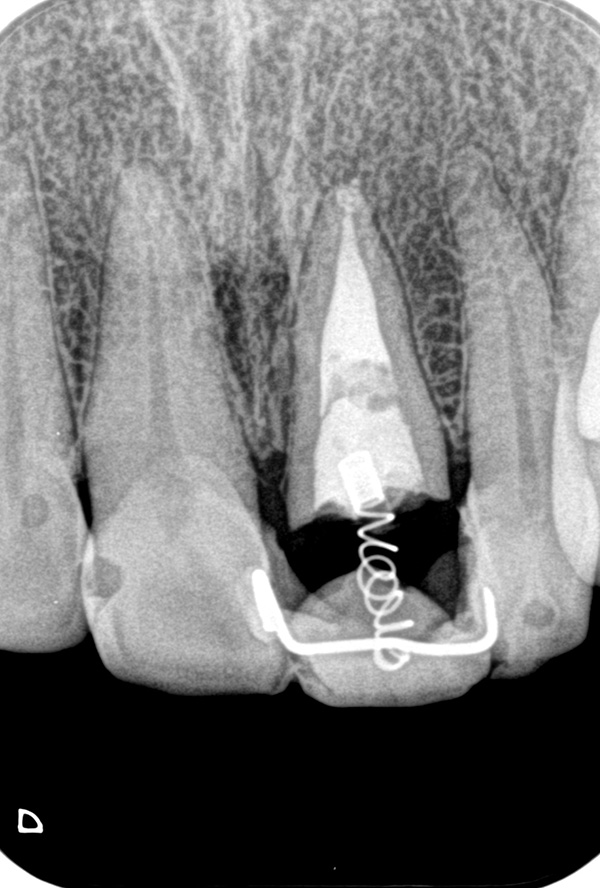

根の奥深くにひび割れが入っていたケース、その位置と深さによって、また周囲の歯質の厚みによっても矯正治療による移動距離や回転角度が異なって参ります。